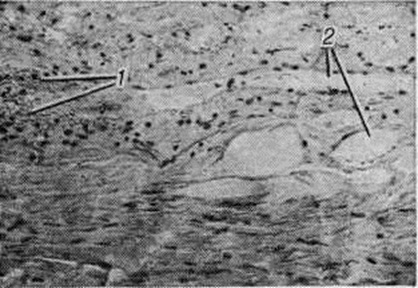

ПахименингитПахименингит (pachymeningitis; греческий pachys толстый, плотный + meninx, meningos оболочка + -itis) — воспаление твёрдой оболочки головного и спинного мозга. Воспалительный процесс твёрдой оболочки головного мозга называют церебральным пахименингитом, а твёрдой оболочки спинного мозга — спинальным пахименингитом. В зависимости от того, какие слои оболочки поражены, различают наружный, внутренний и внутри-оболочечный Пахименингит По характеру воспалительного процесса различают серозный, геморрагический и гнойный Пахименингит, по течению — острый и хронический Пахименингит Патологоанатомические изменения при серозном Пахименингит характеризуются разрыхлением, отёком и резким полнокровием твёрдой оболочки головного и спинного мозга. При геморрагическом внутреннем Пахименингит в патологический процесс вовлекается твёрдая оболочка головного мозга, чаще верхнелатеральной поверхности лобной и височной долей полушария головного мозга, иногда обоих полушарий мозжечка, реже области турецкого седла. В твёрдой оболочке спинного мозга геморрагический внутренний Пахименингит встречается крайне редко. При этой форме происходит геморрагическое пропитывание или расслоение твёрдой оболочки головного мозга вследствие разрыва стенок или флебита мозговых вен в зоне впадения их в синусы твёрдой мозговой оболочки. Макроскопически поражённая оболочка имеет пёстрый вид за счёт чередования буровато-коричневых старых очагов и скопления крови в образующихся в результате повторных кровоизлияний полостях (цветной рисунок 4). В дальнейшем содержимое полостей полностью обесцвечивается и образуются так называемый гигромы твёрдой оболочки головного мозга. Микроскопически при геморрагическом Пахименингит обнаруживаются очаги кровоизлияний разной давности и полости, внутренняя поверхность которых выстлана эндотелием (рисунок 1). Организация геморрагических масс (смотри полный свод знаний: Организация в патологии) происходит путём врастания в них грануляционной ткани с образованием тонкостенных сосудов (рисунок 2). В грануляционной ткани выявляются скопления гемолизированной крови и отложения гемосидерина; в формирующейся фиброзной капсуле отмечается пролиферация макрофагов (рисунок 3). Капсула может быть инфильтрирована лимфоидными и плазматическими клетками. Особенностью геморрагического Пахименингит является медленное развитие процессов организации и недостаточно выраженное свёртывание излившейся крови вследствие малого содержания в ней фибрина или примеси цереброспинальной жидкости. В центральных отделах полостей процессы организации могут развиваться быстрее, что сопровождается в ряде случаев отложением солей кальция или окостенением твёрдой оболочки головного мозга. При гнойном Пахименингит твёрдая оболочка головного и спинного мозга полнокровна, гнойный или фибринозно-гнойный экссудат располагается на наружной поверхности оболочки или в субдуральном пространстве, постепенно подвергаясь организации и отграничению спайками; при этом образуются экстра или субдуральные абсцессы. Микроскопически в твёрдой оболочке головного и спинного мозга обнаруживаются периваскулярные инфильтраты из сегментоядерных лейкоцитов и грануляционная ткань разной степени зрелости. При стихании процесса развивается фиброз оболочки. При хронический Пахименингит развивается фиброз твёрдой оболочки головного и спинного мозга и происходит сращение её с окружающими тканями. Распространение процесса по протяжению твёрдой оболочки спинного мозга способствует образованию муфтообразного утолщения с последующим сдавлением корешков спинномозговых нервов и их атрофией. При туберкулёзе, сифилисе, актиномикозе и других хронический инфекциях встречается хронический гиперпластический Пахименингит. Твёрдая оболочка спинного мозга при этом утолщена за счёт пропитывания желатинозным экссудатом, имеет желтовато-серый цвет, может быть сращена с окружающими тканями. Микроскопически обнаруживаются специфические гранулемы, при сифилисе преобладают гуммозные поражения. Церебральный пахименингит. Различают несколько форм церебрального Пахименингит: серозный церебральный Пахименингит, геморрагический внутренний и внутридуральный Пахименингит, наружный и внутренний гнойный церебральный Пахименингит |